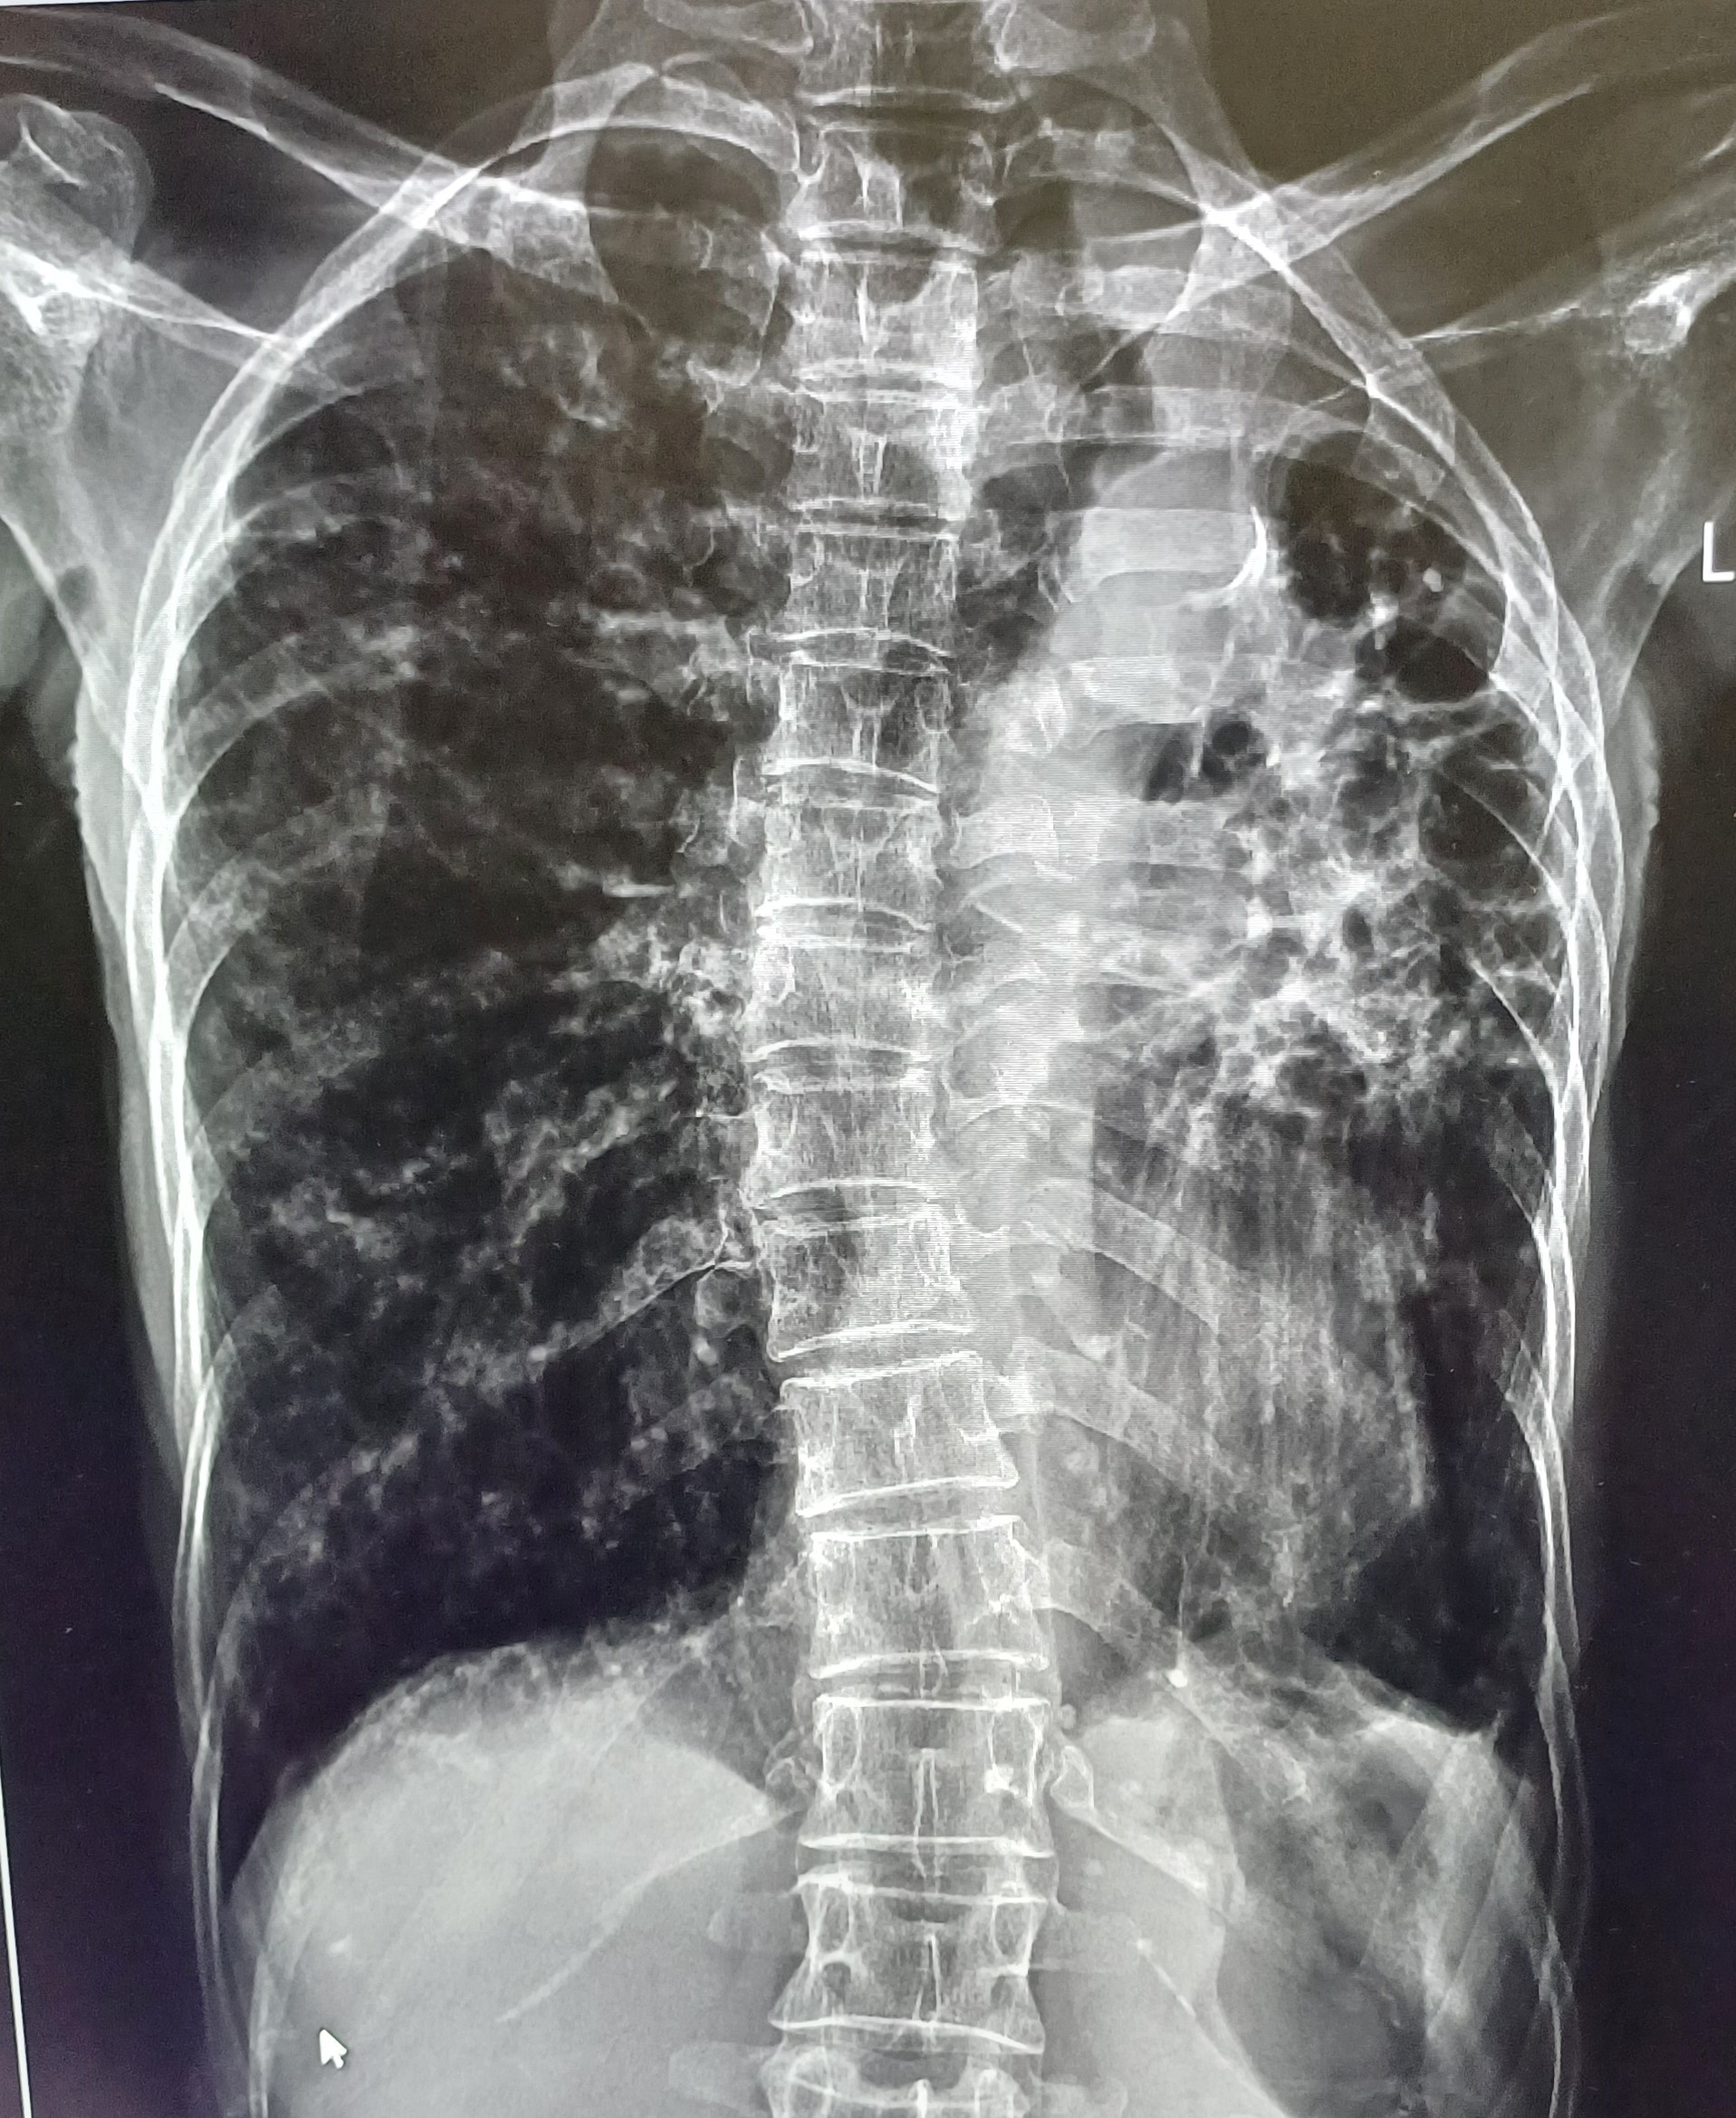

| 60 | IGGMC, Nagpur, Nagpur | P2 | 29-4412 | Ritesh Uikey | Consent taken on Paper | 30 Yrs. |

Provisional Diag : Pulmonary Tuberculosis

Final Diag : Pulmonary Tuberculosis |

TB Case (Confirmed) | Bilateral Lung Infiltration Present & Right Upper Zone Cavity Present | Abnormality visible on x-ray |